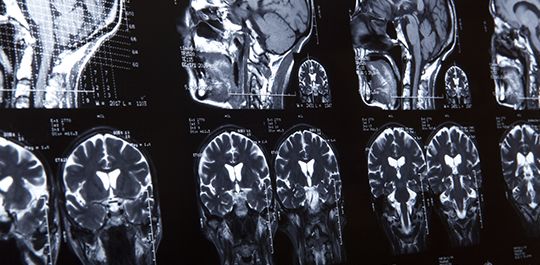

The Mayo Clinic says the use of CT scans and MRI’s after an accident where a brain injury might have occurred will help physicians make a diagnosis in a prompt manner. CT scans can potentially show injuries that otherwise might not be apparent, like bruising or bleeding in the brain. Monitoring the pressure within a person’s skull can potentially let physicians know if the brain is swelling, a very serious symptom of injuries to the brain. Physicians also try to find traditional symptoms of injuries to the brain.